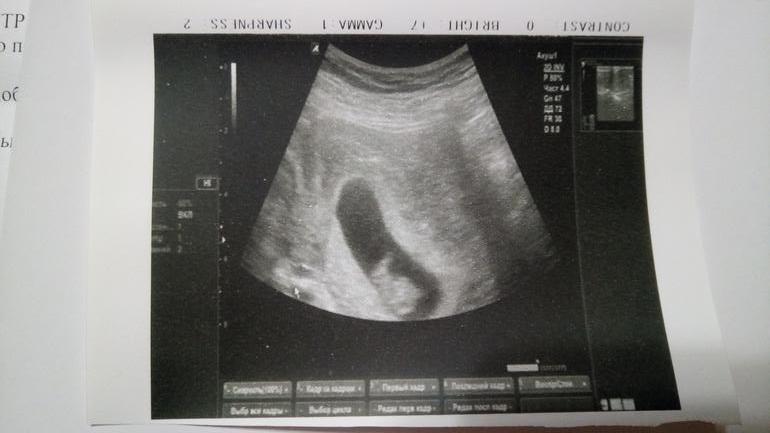

Нам сегодня 8 недель и 5 дней)))

Ходила на узи для уточнения срока,так как скрининг назначили поздно, 12+5 по дню, какой я считаю началом отсчета, по моим подсчетам, овуляция поздняя и всё сдвинулось на неделю ровно. Так и есть. А если вдруг как бывает часто,срок выравнивается с тем,что по М, то было бы поздно для скрининга. Ну все окей)) Теперь буду спокойно ждать 15 ноября))))

А вот и мы.